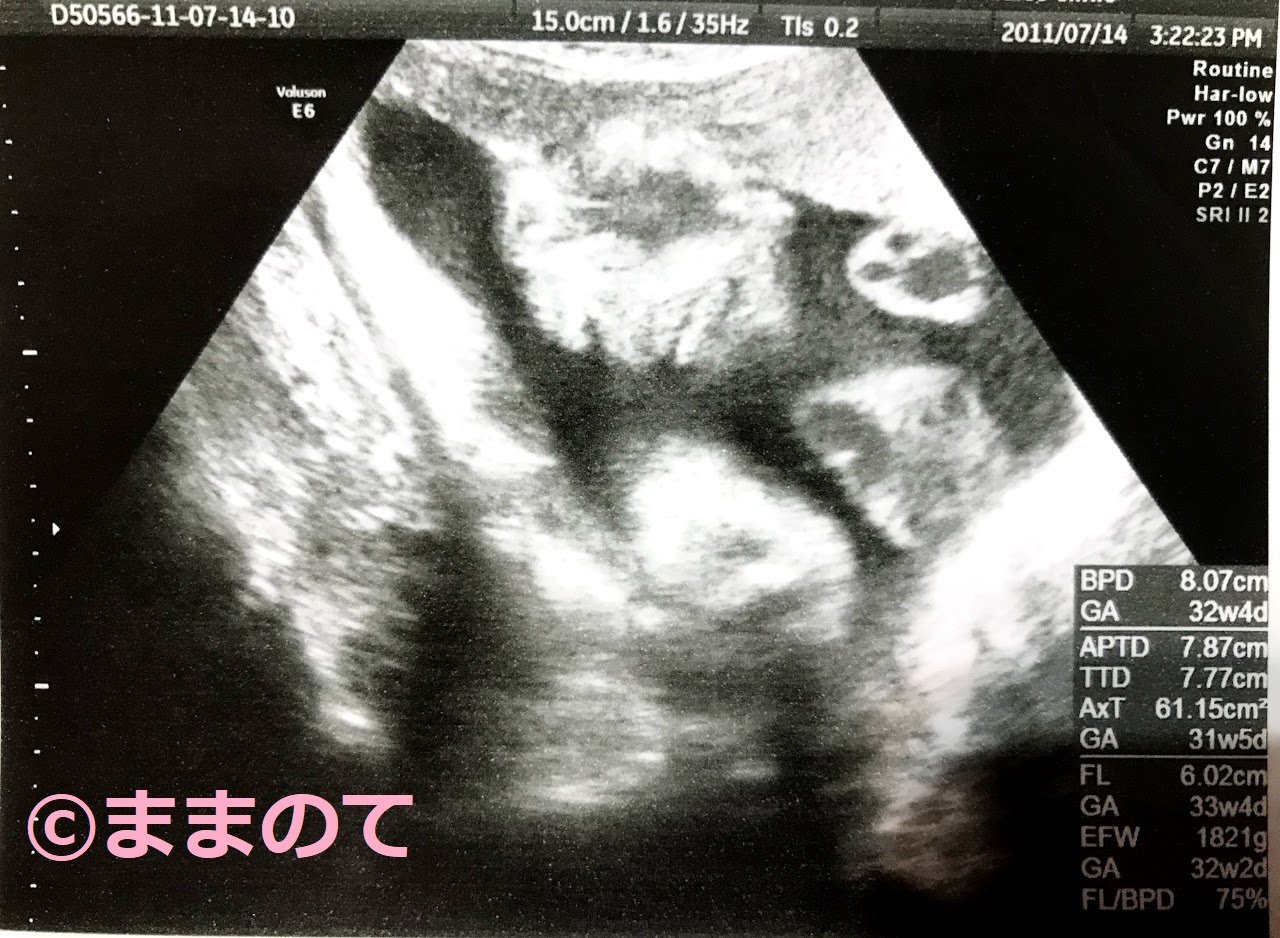

妊娠33週の赤ちゃんのエコー画像

33週4日の胎児です。BPDは8cm、EFWが1821gとやや小柄で、測定値に対応する妊娠週数では32週ですが、妊娠経過に異常はありません。写真には顔が正面にアップで写っています。このころは全身をとらえることができませんが、顔の作りや表情をうかがい知ることができるのがうれしいですね。